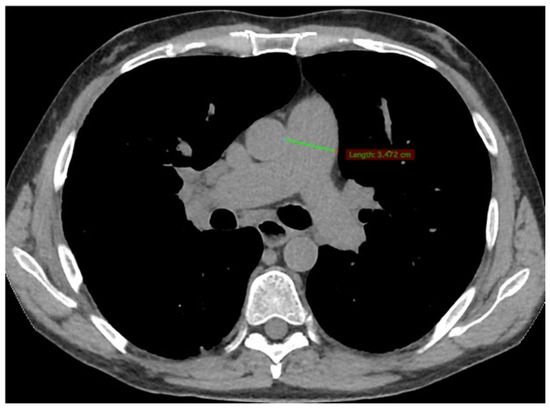

2. Case Presentation